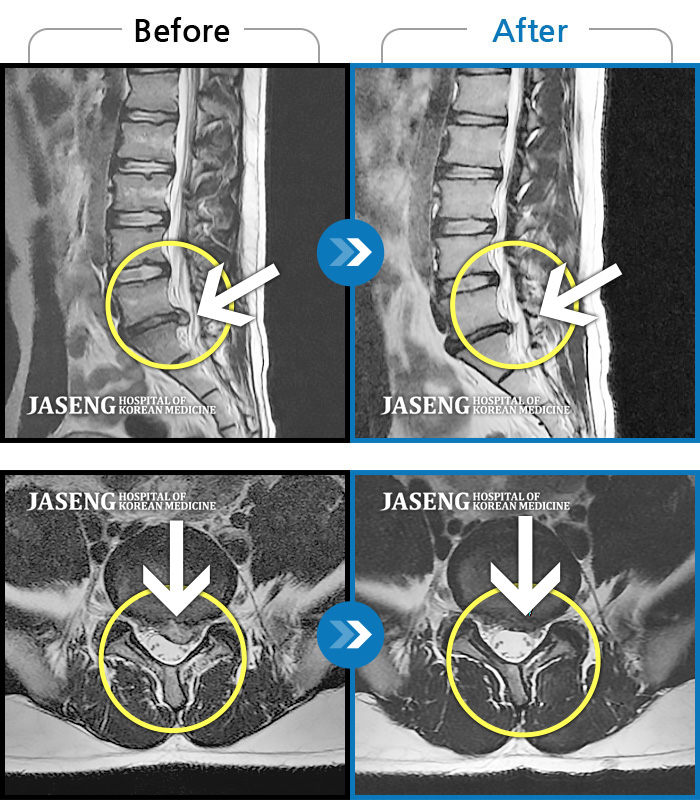

허리디스크

보라매 · 왕오호 원장

허리와 좌측 엉치 통증

촬영시기

2015.12.29 ~ 2018.10.11

2018.12.28